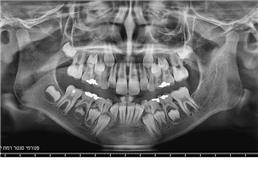

זקוקים לצילומי שיניים וחשוב לכם לקבל מענה מקצועי, אמין, מהיר ויעיל? מכון פנורמי סנטר לשירותכם! כמכון רנטגן מוביל בתחומו, אנו מבצעים צילומי שיניים ולסתות לרבות צילומי CT ואמונים על מתן שירות מקצועי, אדיב, אישי ויעיל לכל לקוח ולקוח. לנוחיותכם, אנו מספקים את מיטב שירותינו באמצעות שלושה סניפים לרבות סניף ברמת ישי, סניף ביוקנעם וסניף במגדל העמק ונשמח לעמוד גם לשירותכם לשביעות רצונכם המלאה!